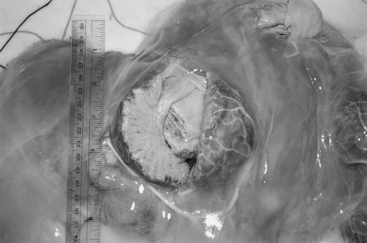

Fig. 55-1 Abnormal cotyledon from the placenta of a cow with hydrallantois (8 months of gestation). The cotyledon, measuring 5 inches in diameter, has been sectioned; note the excessive edema within the intercotyledonary placenta.